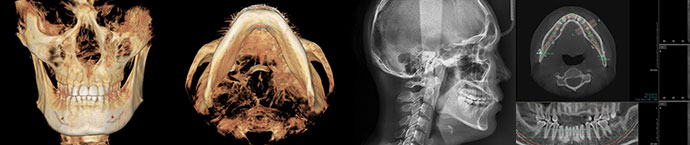

3D-CT / X-RAY

Precision Analysis System

Facial contouring surgery is a highly

complex procedure that requires consideration

of both bone and soft tissues. At VIEW Plastic Surgery,

we utilize high-resolution diagnostic equipment,

including 3D-CT and X-Ray, to thoroughly analyze each

individual's facial features, bone structure and size,

nerve line location, and muscle and fat tissue characteristics.

This precise analysis allows us to carefully develop

a meticulous surgical plan tailored to each patient.

Facial contouring surgery is a highly complex procedure that requires consideration of both bone and soft tissues. At VIEW Plastic Surgery, we utilize high-resolution diagnostic equipment, including 3D-CT and X-Ray, to thoroughly analyze each individual's facial features, bone structure and size, nerve line location, and muscle and fat tissue characteristics. This precise analysis allows us to carefully develop a meticulous surgical plan tailored to each patient.